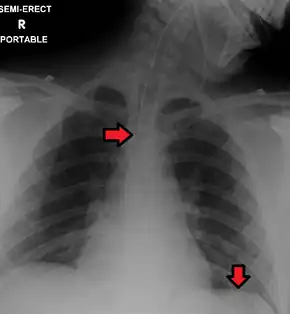

Great care must be taken to ensure that the tube has not passed through the larynx into the trachea and down into the bronchi. The reliable method is to aspirate some fluid from the tube with a syringe. This fluid is then tested with pH paper (note not litmus paper) to determine the acidity of the fluid. If the pH is 4 or below then the tube is in the correct position. If this is not possible then correct verification of tube position is obtained with an X-ray of the chest/abdomen. This is the most reliable means of ensuring proper placement of an NG tube.[6] The use of a chest x-ray to confirm position is the expected standard in the UK, with Dr/ physician review and confirmation. Future techniques may include measuring the concentration of enzymes such as trypsin, pepsin, and bilirubin to confirm the correct placement of the NG tube. As enzyme testing becomes more practical, allowing measurements to be taken quickly and cheaply at the bedside, this technique may be used in combination with pH testing as an effective, less harmful replacement of X-ray confirmation.[7] If the tube is to remain in place then a tube position check is recommended before each feed and at least once per day.